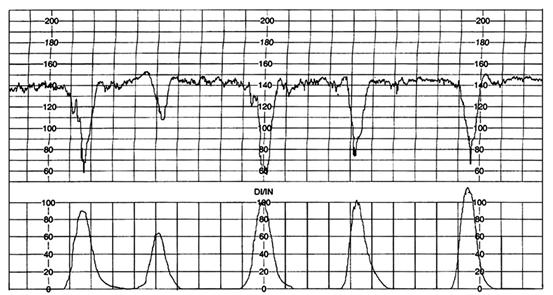

Deceleratiile: Hon 1968 [11] le-a clasificat astfel:

precoce: atribuite compresiei pe craniu

tardive: atribuite insuficientei utero-placentare

variabile: atribuite compresiei pe cordonul ombilical

Deceleratiile variabile : sunt predominante in cursul travaliului si nasterii. Sunt ca forma, durata si amplitudine diferita.

Fig. nr. 308. Deceleratii variabile simultane cu contractiile uterine

Fig. nr. 309. Deceleratiile tardive in asociere cu tachicardie

Caracterele nefavorabile pentru fat a deceleratiilor variabile sunt :

pierderea acceleratiei initiale

revenirea lenta la RCFB

pierderea cresterii secundare a RCF

prelungirea cresterii secundare a RCF

decelerarea bifazica

pierderea variabilitatii in timpul deceleratiei

continuarea RCFB la un nivel mai mare sau mai mic

Fig. nr.310. Deceleratii variabile de durata , cu timp lung al revenirii la RCFB

Deceleratiile tardive sunt repetitive, uniforme, cu o intoarcere inceata la RCFB, ele apar dupa Hon la peste 30 sec dupa inceputul contractiei. Asocierea deceleratiilor tardive cu scaderea variabilitatii si absenta acceleratiilor reprezinta un semn tardiv de deteriorare fetala.